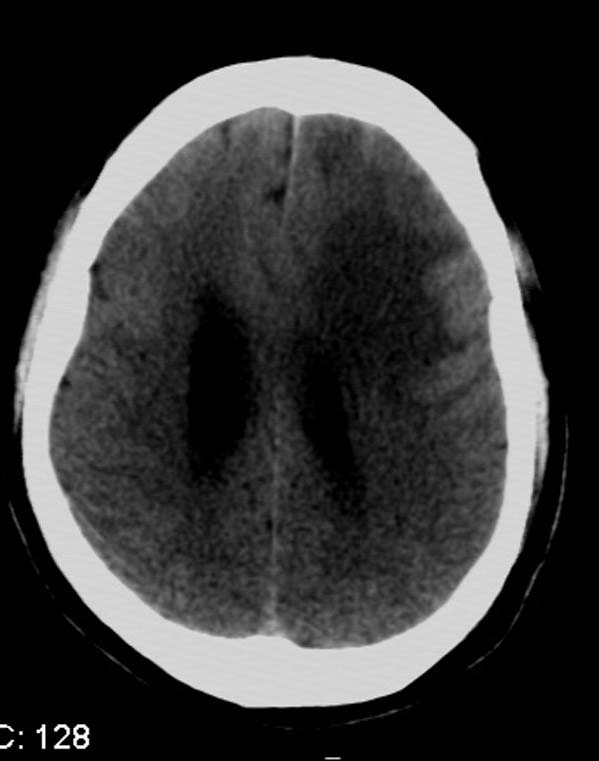

以下是引用拾荒者在2007-10-5 19:31:00的发言:[br]左额叶镰旁不规则形高密度影,中间见钙化灶及略低密度影,占位征象明显,周围有低密度水肿带环绕,首先考虑脑膜瘤。